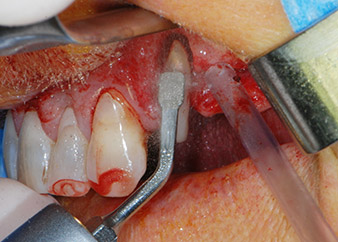

Prior to implant placement, infected tissue was removed from the alveolar bone in the implant site and around the abutment teeth with an insert originally designed for bone shaping and collecting bone chips (Piezomed, insert B5) (Figs. 6 and 7).

osseous defects

Fig. 7: After cleaning the osseous defects mesial to tooth 27 and around the root of tooth 24 were clearly visible.